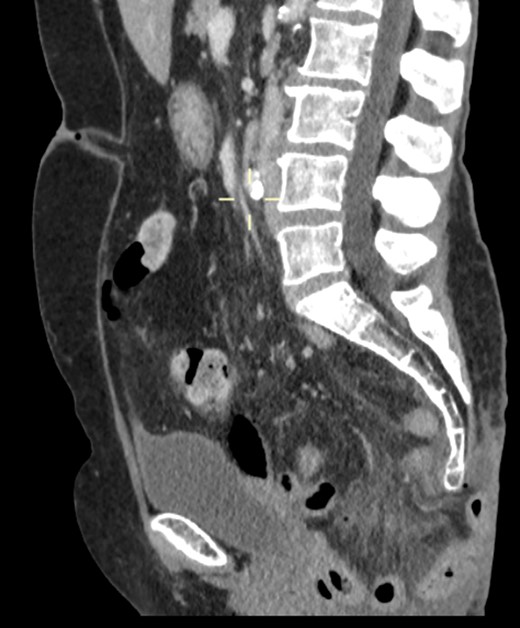

On examination, she was febrile. Her abdomen was generally tender. Bowel sounds were present and up to that time her stoma was working. Her perineal hernia was red and tender. Her initial CXR (Fig. 1) did reveal a sliver of gas underneath her right hemidiaphragm and in keeping with her abdominal findings she progressed to further imaging. CT abdomen pelvis with contrast showed pneumoperitoneum (Fig. 2) with ‘a tiny pocket of air is also seen adjacent to a loop of bowel in the pelvis posterior to the bladder’. ‘Exact site of perforation has not been demonstrated but could possibly be in the bowel loops in the perineum’ (Figs 3 and 4).

CT showing small bowel loops in pelvis with perineal hernia and free fluid.

Sagittal view showing small bowel loops in pelvis with perineal hernia.